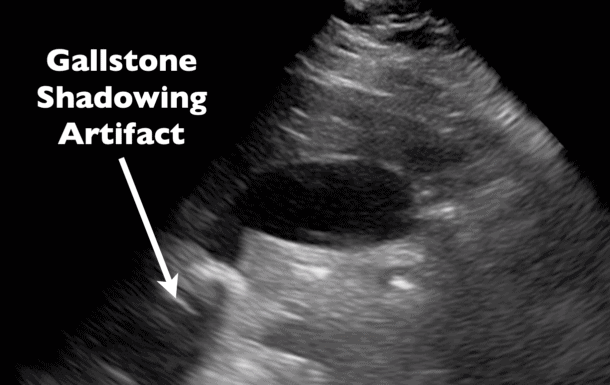

Problema #4: "¡Hay un vacío negro detrás de algo!"

Esto es Acoustic Shadowing.

Piensa en una gran roca en un río. El agua fluye a su alrededor, pero justo detrás de la roca hay un lugar tranquilo.

Los ultrasonidos funcionan del mismo modo. Cuando las ondas sonoras chocan contra algo muy denso (como un cálculo biliar o una costilla), no pueden atravesarlo. Esto deja tras de sí una "sombra" negra y sin señal.